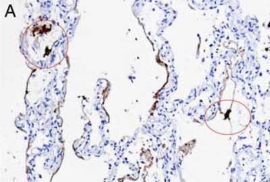

检测肺部组织中的SARS-CoV-2

|

检测SARS-CoV-2 RNA。A和B分别为使用竞品和Enzo探针在COVID-19肺炎样品中进行SARS-CoV-2 RNA原位杂交。竞品探针还会标记巨噬细胞(图A中圆圈部分)。

Nuovo GJ et Al. Appl Immunohistochem Mol Morphol. 2022 Feb 1;30(2):83-90.